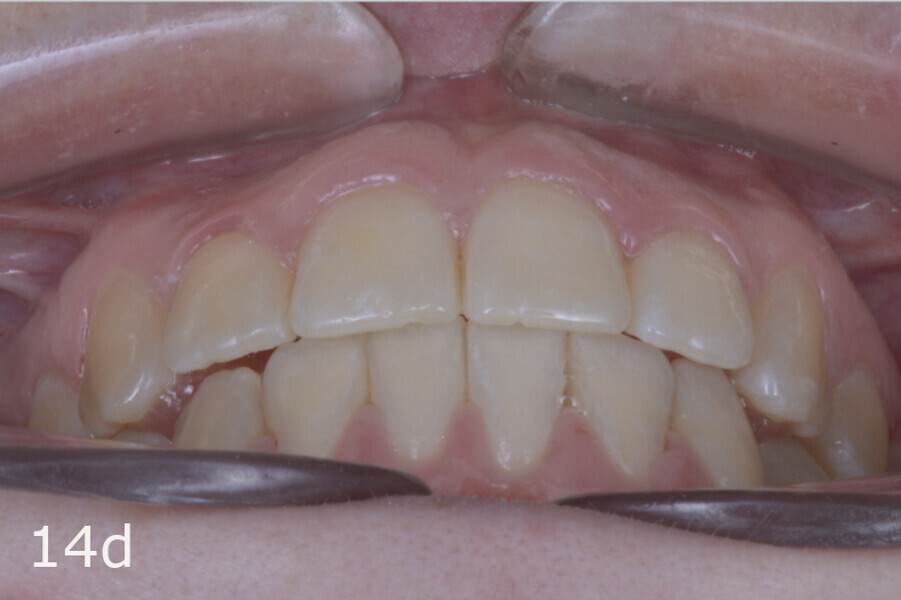

The total treatment time was 15 months. An Angle Class I relationship was established along with adequate anterior and canine guidance, establishing a functional occlusion. This not only ensures optimal masticatory function but also protects the teeth and the temporomandibular joint from excessive force. Maxillary and mandibular fixed retention were installed at the end of the treatment (Figs. 13–19).